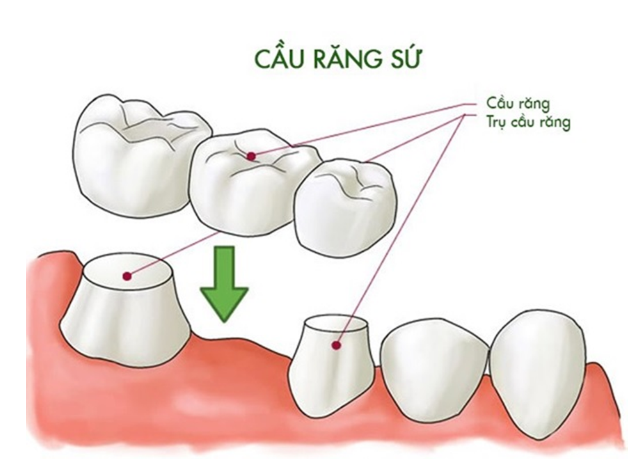

Một chiếc cầu răng tiêu chuẩn thường bao gồm ba phần chính:

- Mão răng (Crowns): Là hai chiếc răng sứ được thiết kế để đặt lên hai chiếc răng thật khỏe mạnh ở hai bên khoảng trống mất răng. Hai chiếc răng này đóng vai trò như trụ cầu, hay còn gọi là trụ đỡ.

- Nhịp cầu (Pontic): Là chiếc răng giả nằm giữa hai mão răng, có nhiệm vụ lấp đầy khoảng trống của chiếc răng đã mất. Chiếc răng này được thiết kế sao cho có hình dáng và màu sắc giống hệt với răng tự nhiên.

Nguyên tắc phục hình của cầu răng là sử dụng các răng thật khỏe mạnh lân cận làm điểm tựa để nâng đỡ và giữ chắc chiếc răng giả ở vị trí bị khuyết. Để làm được điều này, nha sĩ sẽ mài nhỏ hai chiếc răng trụ để làm cùi răng, sau đó gắn mão răng và nhịp cầu lên trên.

- Cầu răng sứ truyền thống: Đây là loại phổ biến nhất. Nó phù hợp với trường hợp hai bên khoảng trống mất răng đều có răng thật khỏe mạnh. Phương pháp này mang lại độ bền chắc cao, giúp phục hồi chức năng ăn nhai hiệu quả.